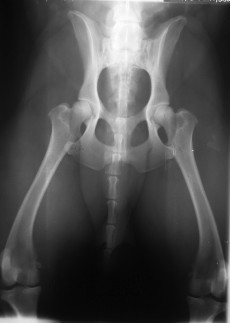

Posizionamento errato per il controllo della displasia dell’anca:

| Asimmetria del bacino. Il lato del bacino in cui il ramo dell’ileo appare più stretto è sollevato dal tavolo radiografico, mentre quello che appare più largo è inclinato verso il tavolo. L’asimmetria del bacino comporta una errata valutazione della congruenza articolare e dell’angolo di Norberg perché migliora artificiosamente la congruenza articolare del lato sollevato e peggiora quella del lato abbassato. |

Mancato parallelismo dei femori tra di loro che appaionoabdotti e divergenti. Ciò aumenta artificiosamente la congruenza articolare e nasconde un’eventuale lassità articolare. |

![]() |